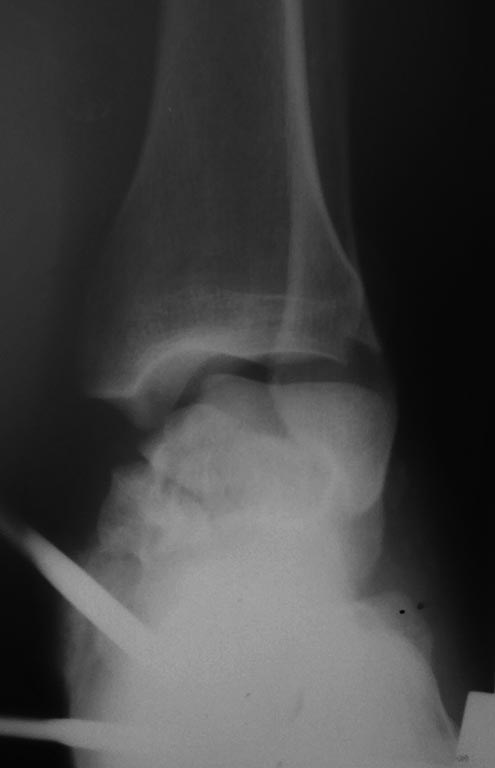

[Ortho] Перелом тела таранной кости.Первичнй артродез .

Пациент С. 28 лет строитель с вредными привычками,пострадал 1 05 17.

Стабилизировали в АВФ,лечим мягкие ткани.По нашему мнению, положительные

результаты (особенно отдаленные) реконструктивных операций при подобных

повреждениях - сомнительны, склоняемся к первичному артродезированию

ретроградным стержнем.Каковы Tips & Tricks,в данной ситуации, необходимо

учесть? Какова вероятность лизиса девитализированных фрагментов,

ипонадобится ли в последующем костная пластика?